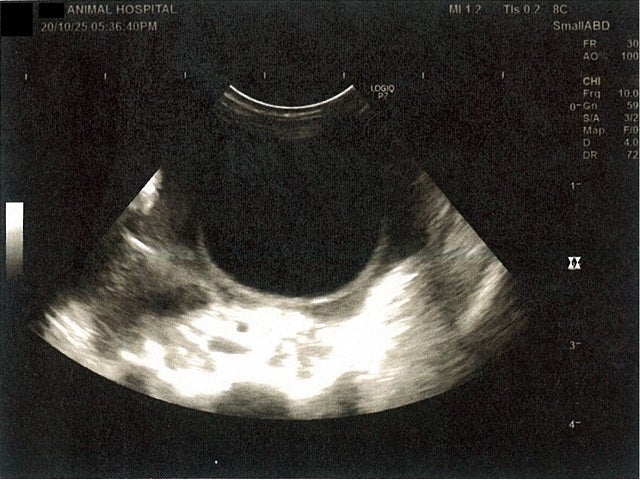

《心臓周りの胸部以外の全ての腹部で腹水がみられるとの診断です》

大網という部分で内臓を包む膜のようなものです。その周りに腹水が溜まっています。

左腎臓周りに腹水が確認できるエコー写真